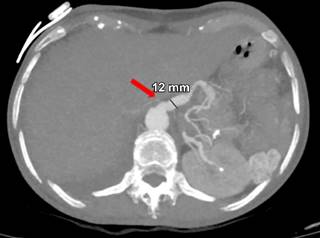

Mujer de 44 años quien 6 meses previos a su ingreso refiere disminución progresiva de la clase funcional debido a un soplo aórtico, por lo que se realizó cambio valvular con la necesidad de ser sometida a circulación extracorpórea y uso de vasopresores. Durante los primeros 10 días postquirúrgicos se diagnostica obstrucción intestinal, por lo que se realiza TC con hallazgo incidental de arteria esplénica (Figura 1) con dilatación aneurismática de hasta 12 mm, en un nuevo estudio de TC a las 24 horas (Figura 2) con ligero aumento del diámetro de aneurisma esplénico hasta 15 mm, pasadas 96 horas solicita nueva TC (Figura 3) y se evidencia mejor definición de la dilatación aneurismática de la arteria esplénica con diámetro actual de 15 mm (previamente de 12 mm). Con los hallazgos tomográficos previamente descritos, se pudo observar la evolución del proceso de dilatación aneurismática con ruptura contenida por el parénquima pancreático, la paciente cursó con un cuadro de obstrucción intestinal con desimpactación endoscópica y dolor abdominal, por lo que seguramente se enmascaró el cuadro clínico.

Figura 2: Tomografía computarizada a las 24 horas con ligero aumento del diámetro del aneurisma esplénico a 15 mm.